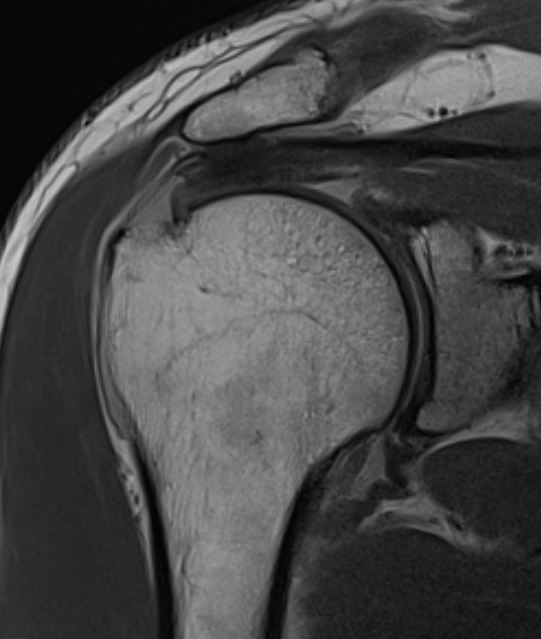

MRI

Look for

- supraspinatus / infraspinatus / subscapularis / long head of biceps pathology

- partial verus full thickness

- size of tear in coronal and sagittal planes

- retraction

- atrophy / fatty infiltration

Full thickness rotator cuff tears